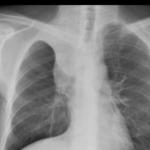

Sarcoid

Album: Sarcoid

Date: 04/20/2004

Size: 63 items

Views: 38682